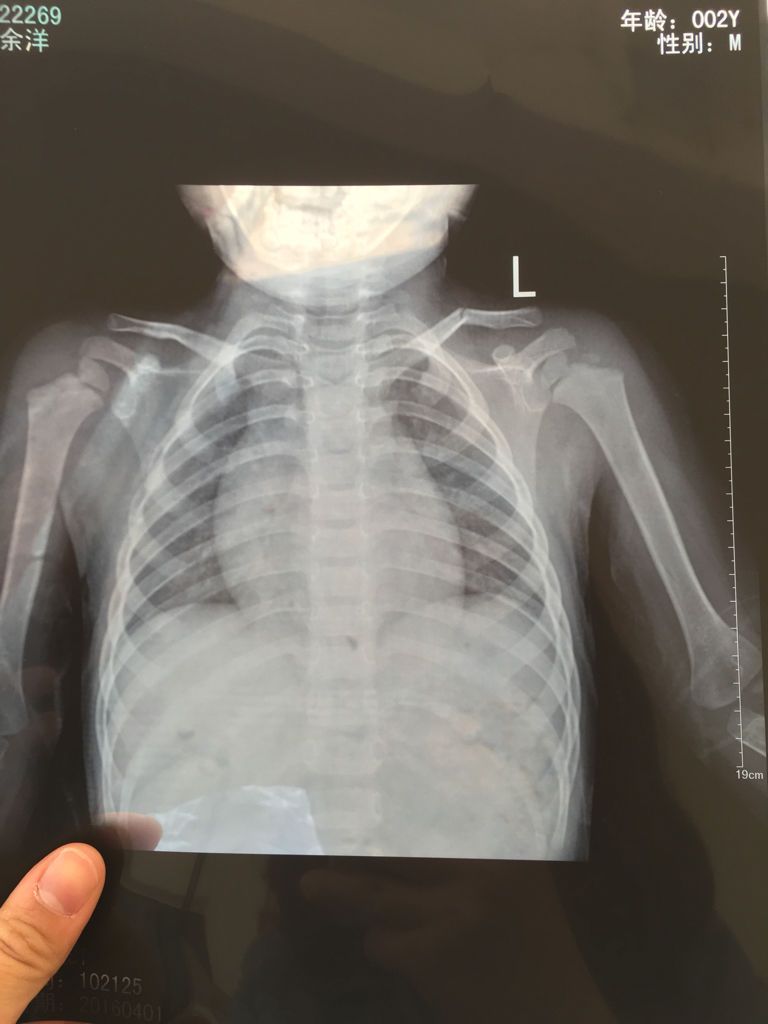

宝宝2岁半,昨天晚上睡觉从床上摔下来,一直哭,今天到拍片子是锁骨骨折,但是我们这的医生说不用固定也 宝宝2岁半,昨天晚上睡觉从床上摔下来,一直哭,今天到拍片子是锁骨骨折,但是我们这的医生说不用固定也不用做什么,骨头会自己愈合,这样真的可以吗 点击展开 匿名用户 2016-04-01 11:15 推荐回答 医生话是对的,不放近宝心也劳抓可找其他专慕宝抗家再看看,孩了健康第一。给采纳 华雄40 2016-04-01 11:17 宝宝知道提示您:回答为网友贡献,仅供参考。 相关问题 一岁半小孩,从床上摔下来 锁骨骨折了 这是当时拍的片子 县里的医生说让在家躺着,并且没有做任何治疗 想请问有过类似经历的宝爸宝妈,还有医生老师 我家宝宝今天20天,昨天睡觉不老实,睡一会儿又醒,抱在 宝宝四个月了,最近两晚总是大哭,还抓耳朵,去医院看了医生说没有事,可他每晚睡觉的时候都抓都哭,把耳